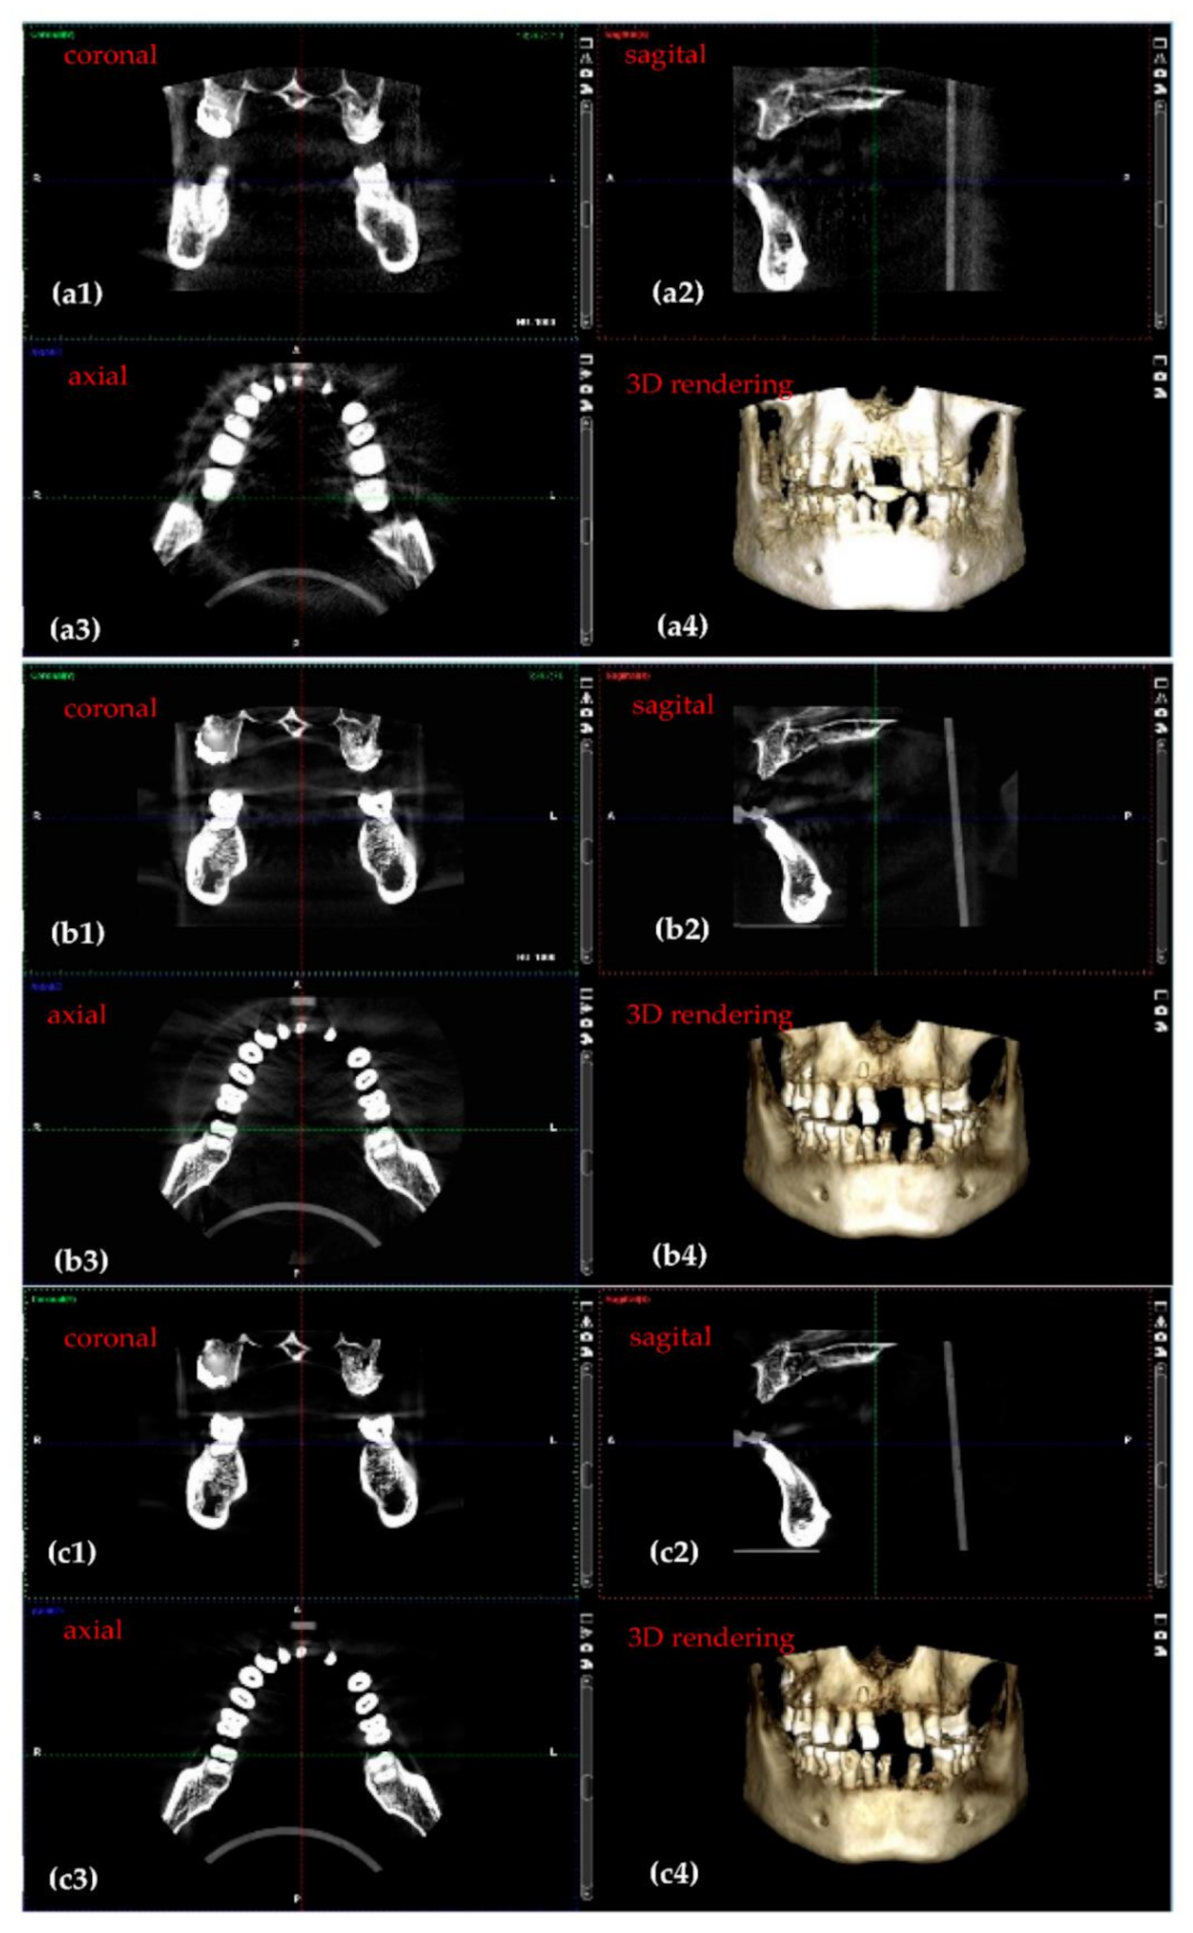

3.2. Optimized Protocol with OCT. 3D CBCT Calibration

| 3D CBCT Radiographs (Figure 9) | Anode Voltage (kV) | Current Intensity (mA) | Exposure Time (s) | Radiation Dose (µSv) |

|---|---|---|---|---|

| a | 60 | 1 | 4.95 | 1.25 |

| b | 75 | 8 | 5.09 | 25.87 |

| c | 90 | 14 | 5.08 | 86.37 |

|

3D CBCT (Figure 9) | ||||

| a | 552 | 2808 | 1680 | 0.67 |

| b | 302 | 2802 | 1552 | 0.8 |

| c | 296 | 3032 | 1664 | 0.82 |